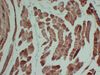

Actin Mouse Monoclonal Antibody [Clone ID: 8B10-3F7-1B8] TA385598 USD 380.00 4 Weeks Sacomeric Muscle Actin (8B10) Mouse monoclonal Antibody Applications IHC Reactivities Human Conjugation Unconjugated 1 / 6 2 / 6 3 / 6 4 / 6 5 / 6 6 / 6 Previous Next